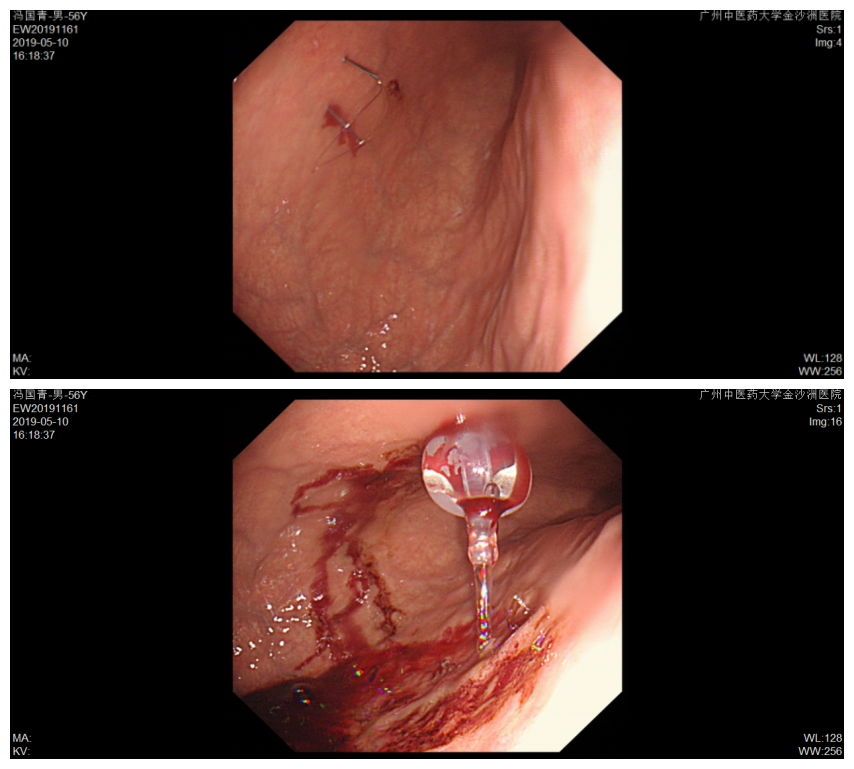

造瘘管内部观

管腔通畅,仅少许渗血